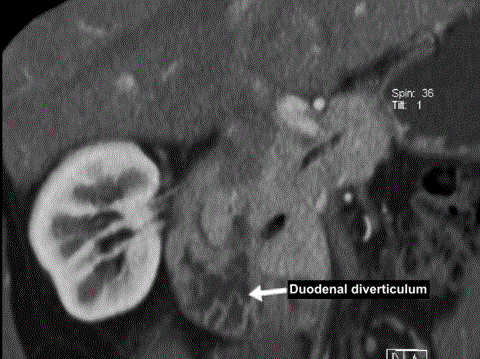

Image 5